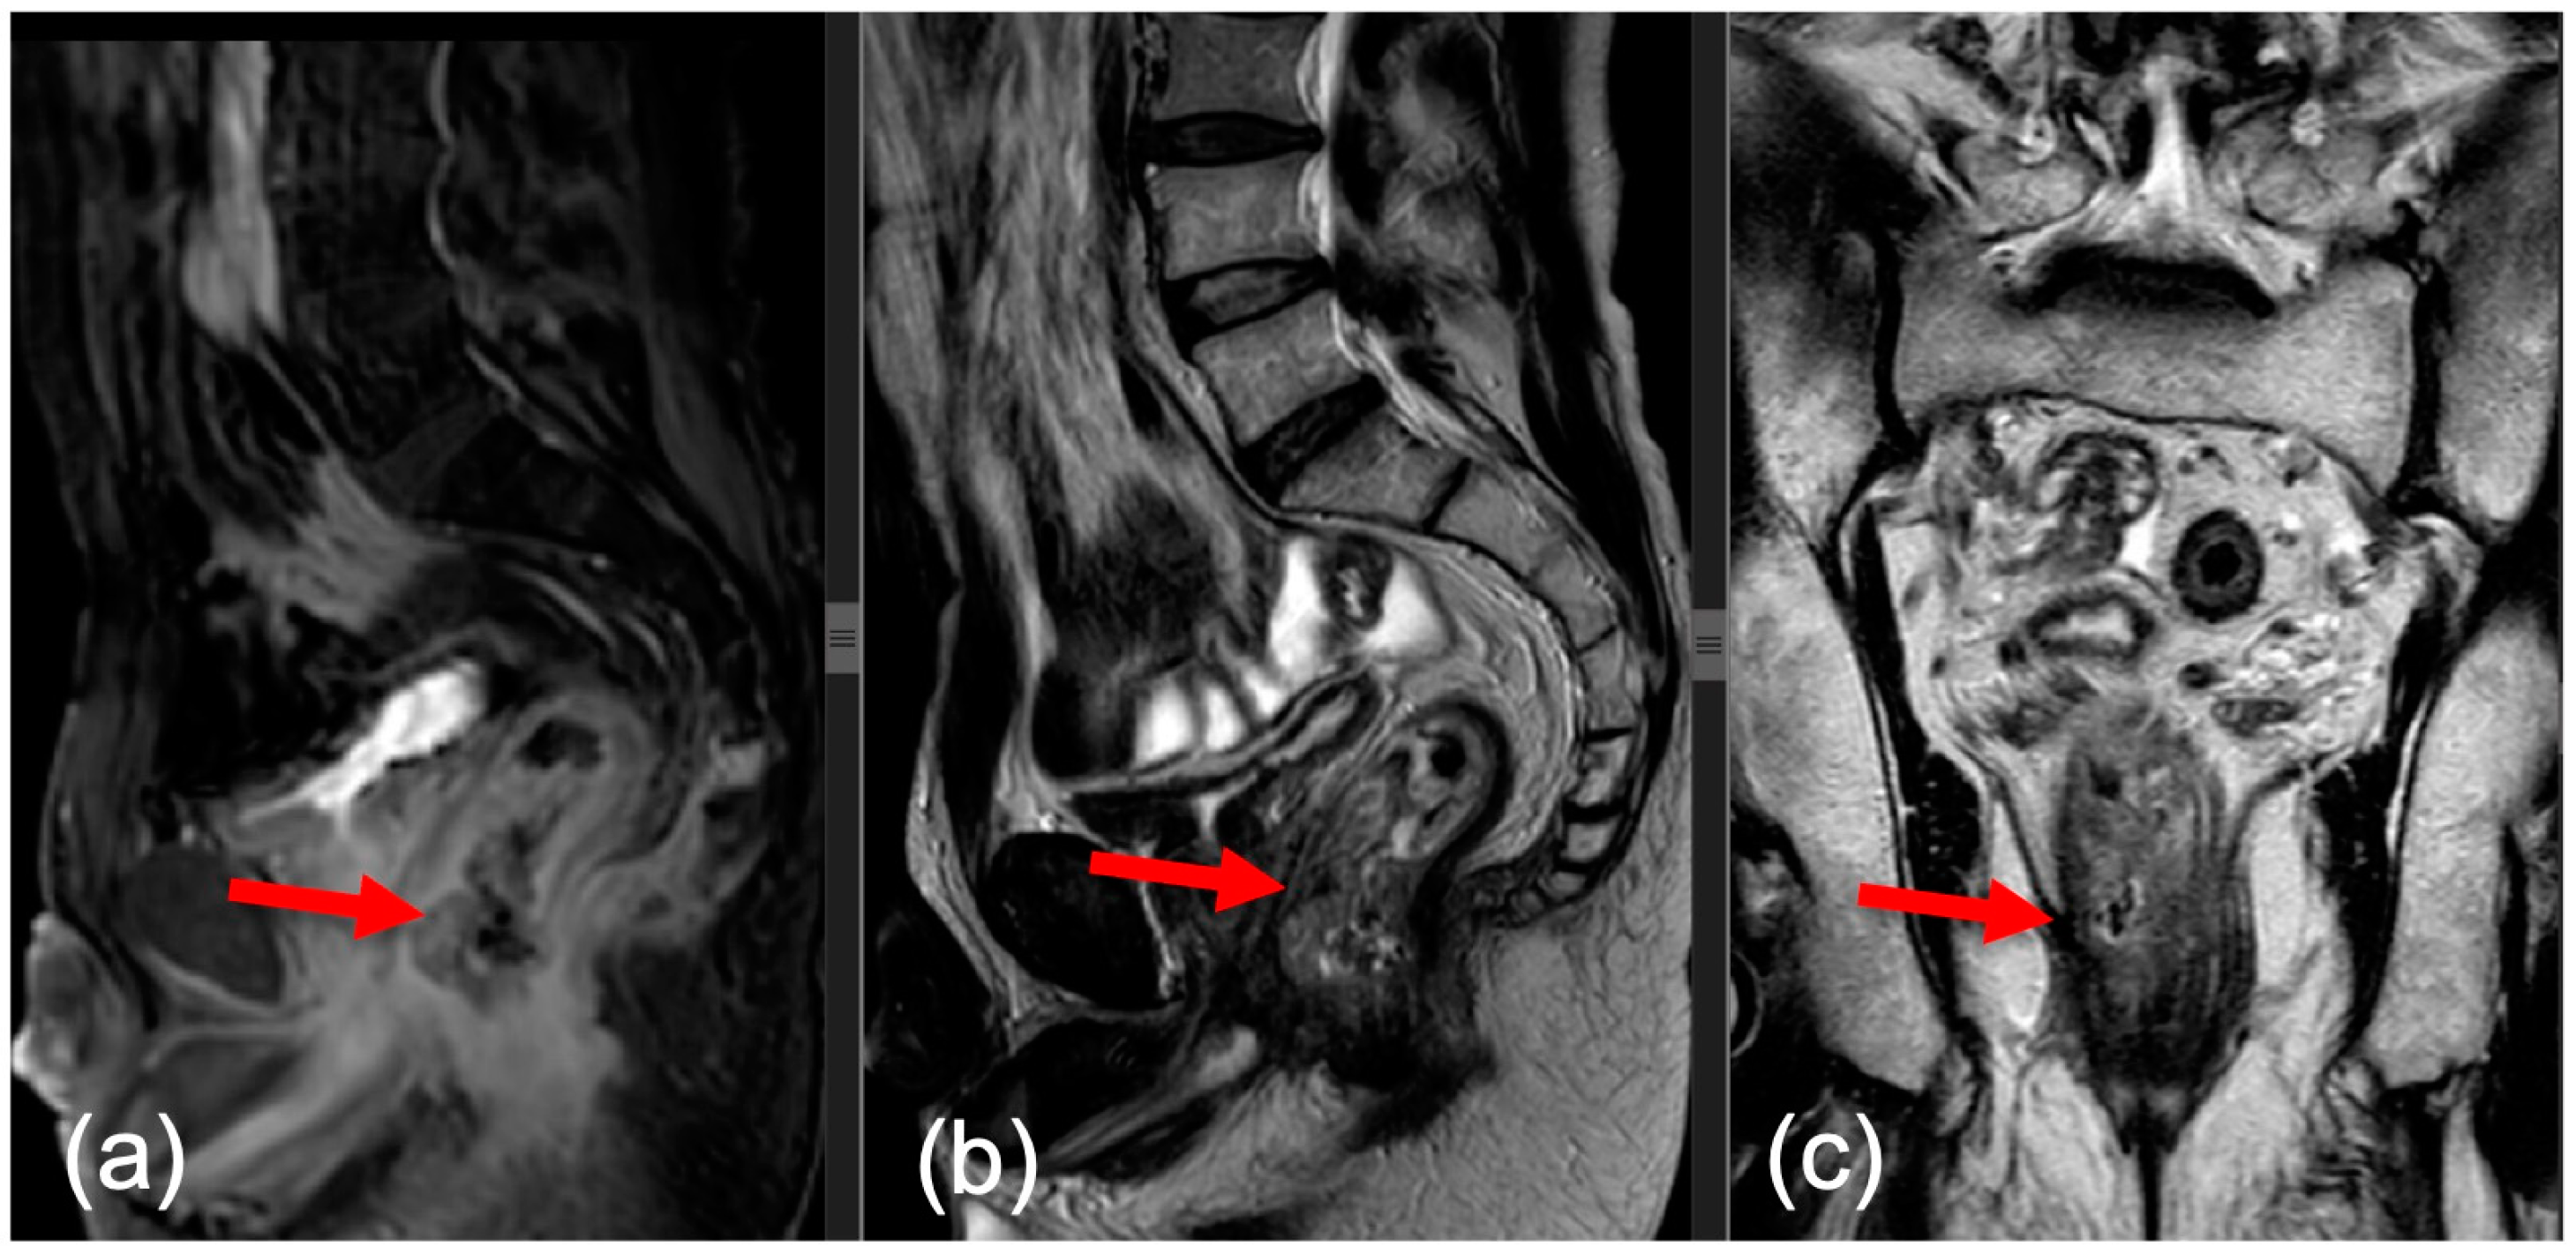

- Sagittal—this plane is used to locate the tumor and to plan the axial and coronal sequences;

- Axial—the plane is angled perpendicular to the tumor to correctly visualize the extension of the tumor against the rectal wall, as well as the distance between the tumor and the mesorectal fascia (MRF);

- Coronal—the plane is angled parallel to the axis of the tumor, which is perpendicular to the axial series.